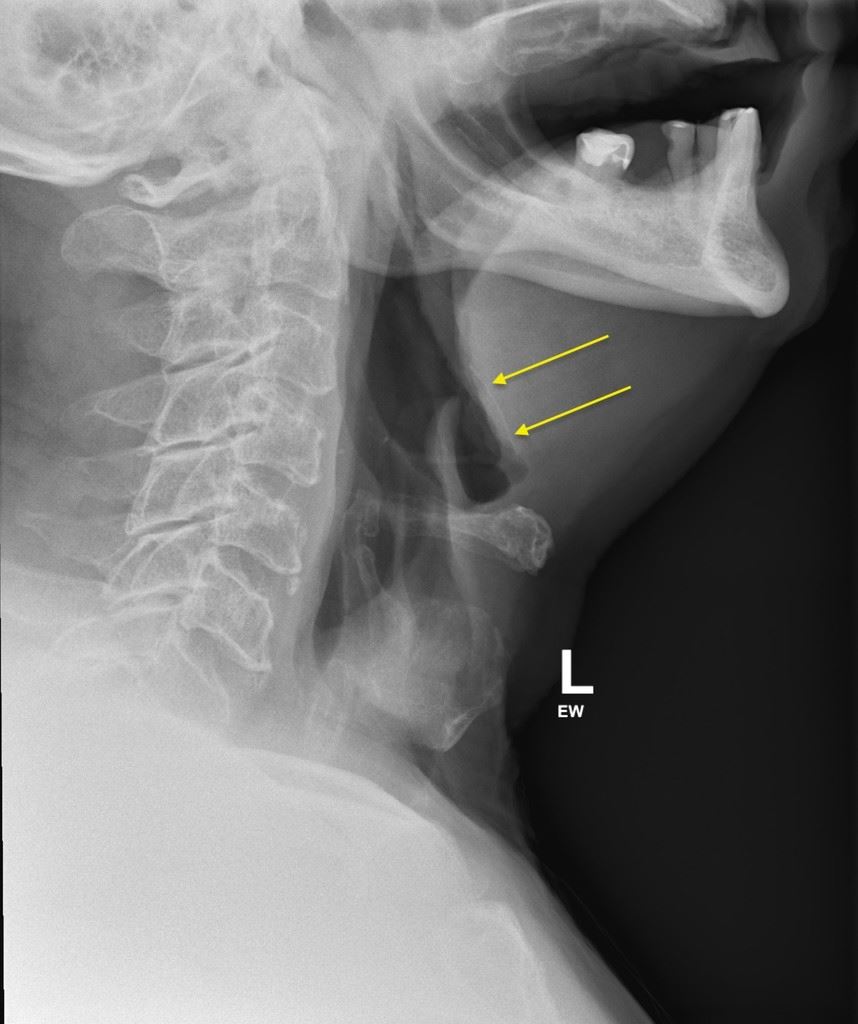

Walau bagaimanapun, apabila rasa itu berterusan, dia akur dan akhirnua pergi berjumpa doktor. Doktor kemudian mengesahkan bahawa ada tulang ayam kecil tersekat pada lehernya, tetapi meyakinkannya bahawa itu bukanlah masalah yang serius.

Namun satu kejutan baginya apabila pakar Telinga, Hidung, dan Tekak (ENT) mencadangkan agar dia minum empat tin air bergas untuk mencairkan tulang tersebut. Dia mendapati ubat tersebut satu rawatan yang unik, tetapi memutuskan untuk mencubanya. Dia kemudian membeli empat tin air bergas dari pasaraya dan terkejut apabila dia berasa lebih baik pada keesokan paginya. Pada hari berikutnya, dia sudah kembali seperti biasa.